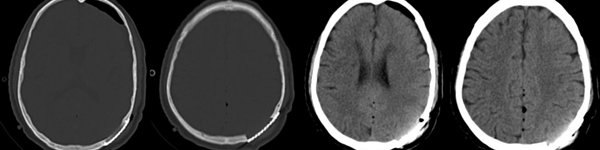

头颅CT检查:

三维重建可见明显颅骨破坏区域

术中可见肿瘤组织位于切口中心,予以完整切除并修补硬膜缺损。根据3D打印支架形态,个体化设计钛网材料行颅骨缺损修补术后复查头颅CT,左顶部肿瘤全切除,左顶部颅骨缺损一期钛网修补完好。

术前及术后颅骨三维重建对比